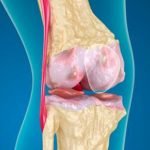

الفصال العظمي

هذه الإصابات المرضية تحدث للغضاريف الموجودة في أطراف العظام، والتي تحدث فيها بعض الإصابات الخطيرة خاصة في الحالات التي تعاني من التقدم في السن، حيث يحدث خلل في تركيب الغضروف مما يؤدي لاحتكاك العظام في المفاصل ببعضها البعض، وبالتالي تحدث إصابات بالفصال العظمي، وبالتالي تحدث التهابات للمفاصل التنكسية وتتضمن أعراض التهابات أحد مفاصل الكتف، مثل الآلام والانتفاخات والتصلب وغيرها.